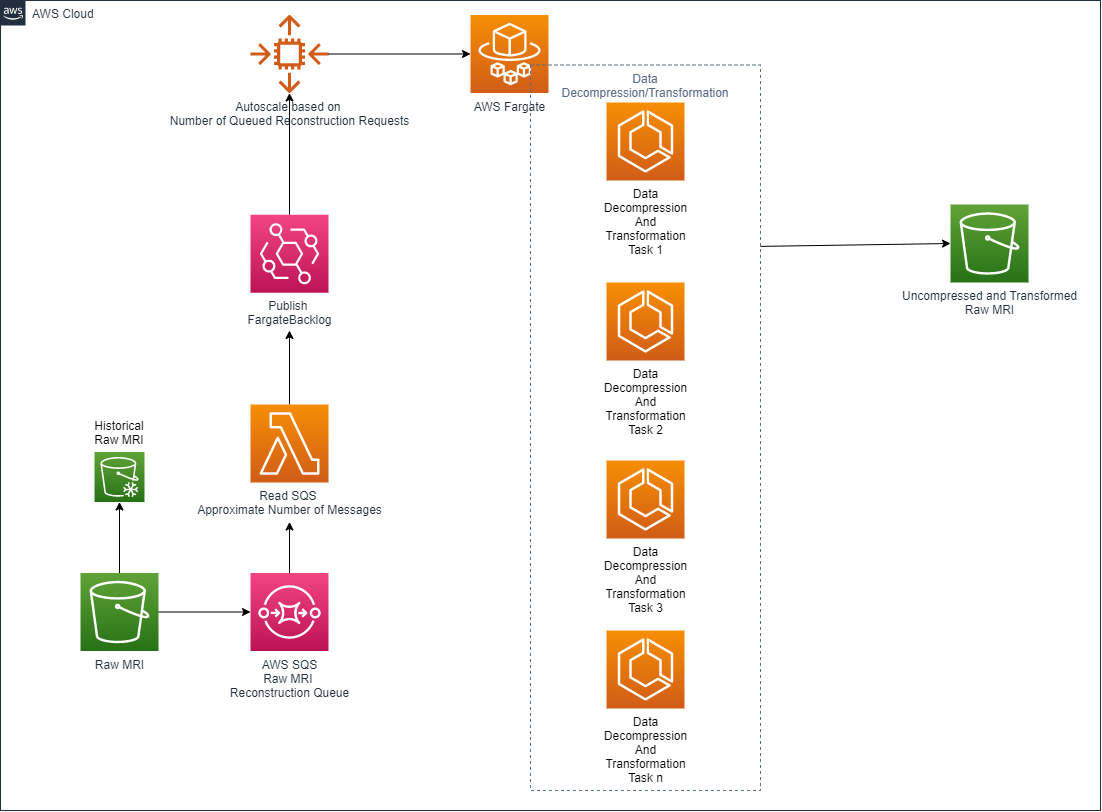

The adopted architecture is outlined in the following figure.

In this architecture, raw MRI data lands in the raw MRI S3 bucket, thereby triggering a new entry in Amazon Simple Queue Service (Amazon SQS).

An AWS Lambda function retrieves the raw MRI Amazon SQS queue depth, which represents the amount of raw MRI acquisitions uploaded to the AWS Cloud. This is used with AWS Fargate to automatically modulate the size of an Amazon Elastic Container Service (Amazon ECS) cluster.

This architecture approach lets it automatically scale up and down accordingly to the number of raw scans landed into the raw input bucket.

After the raw MRI data is decompressed and preprocessed, it’s saved into another S3 bucket so that it can be reconstructed.